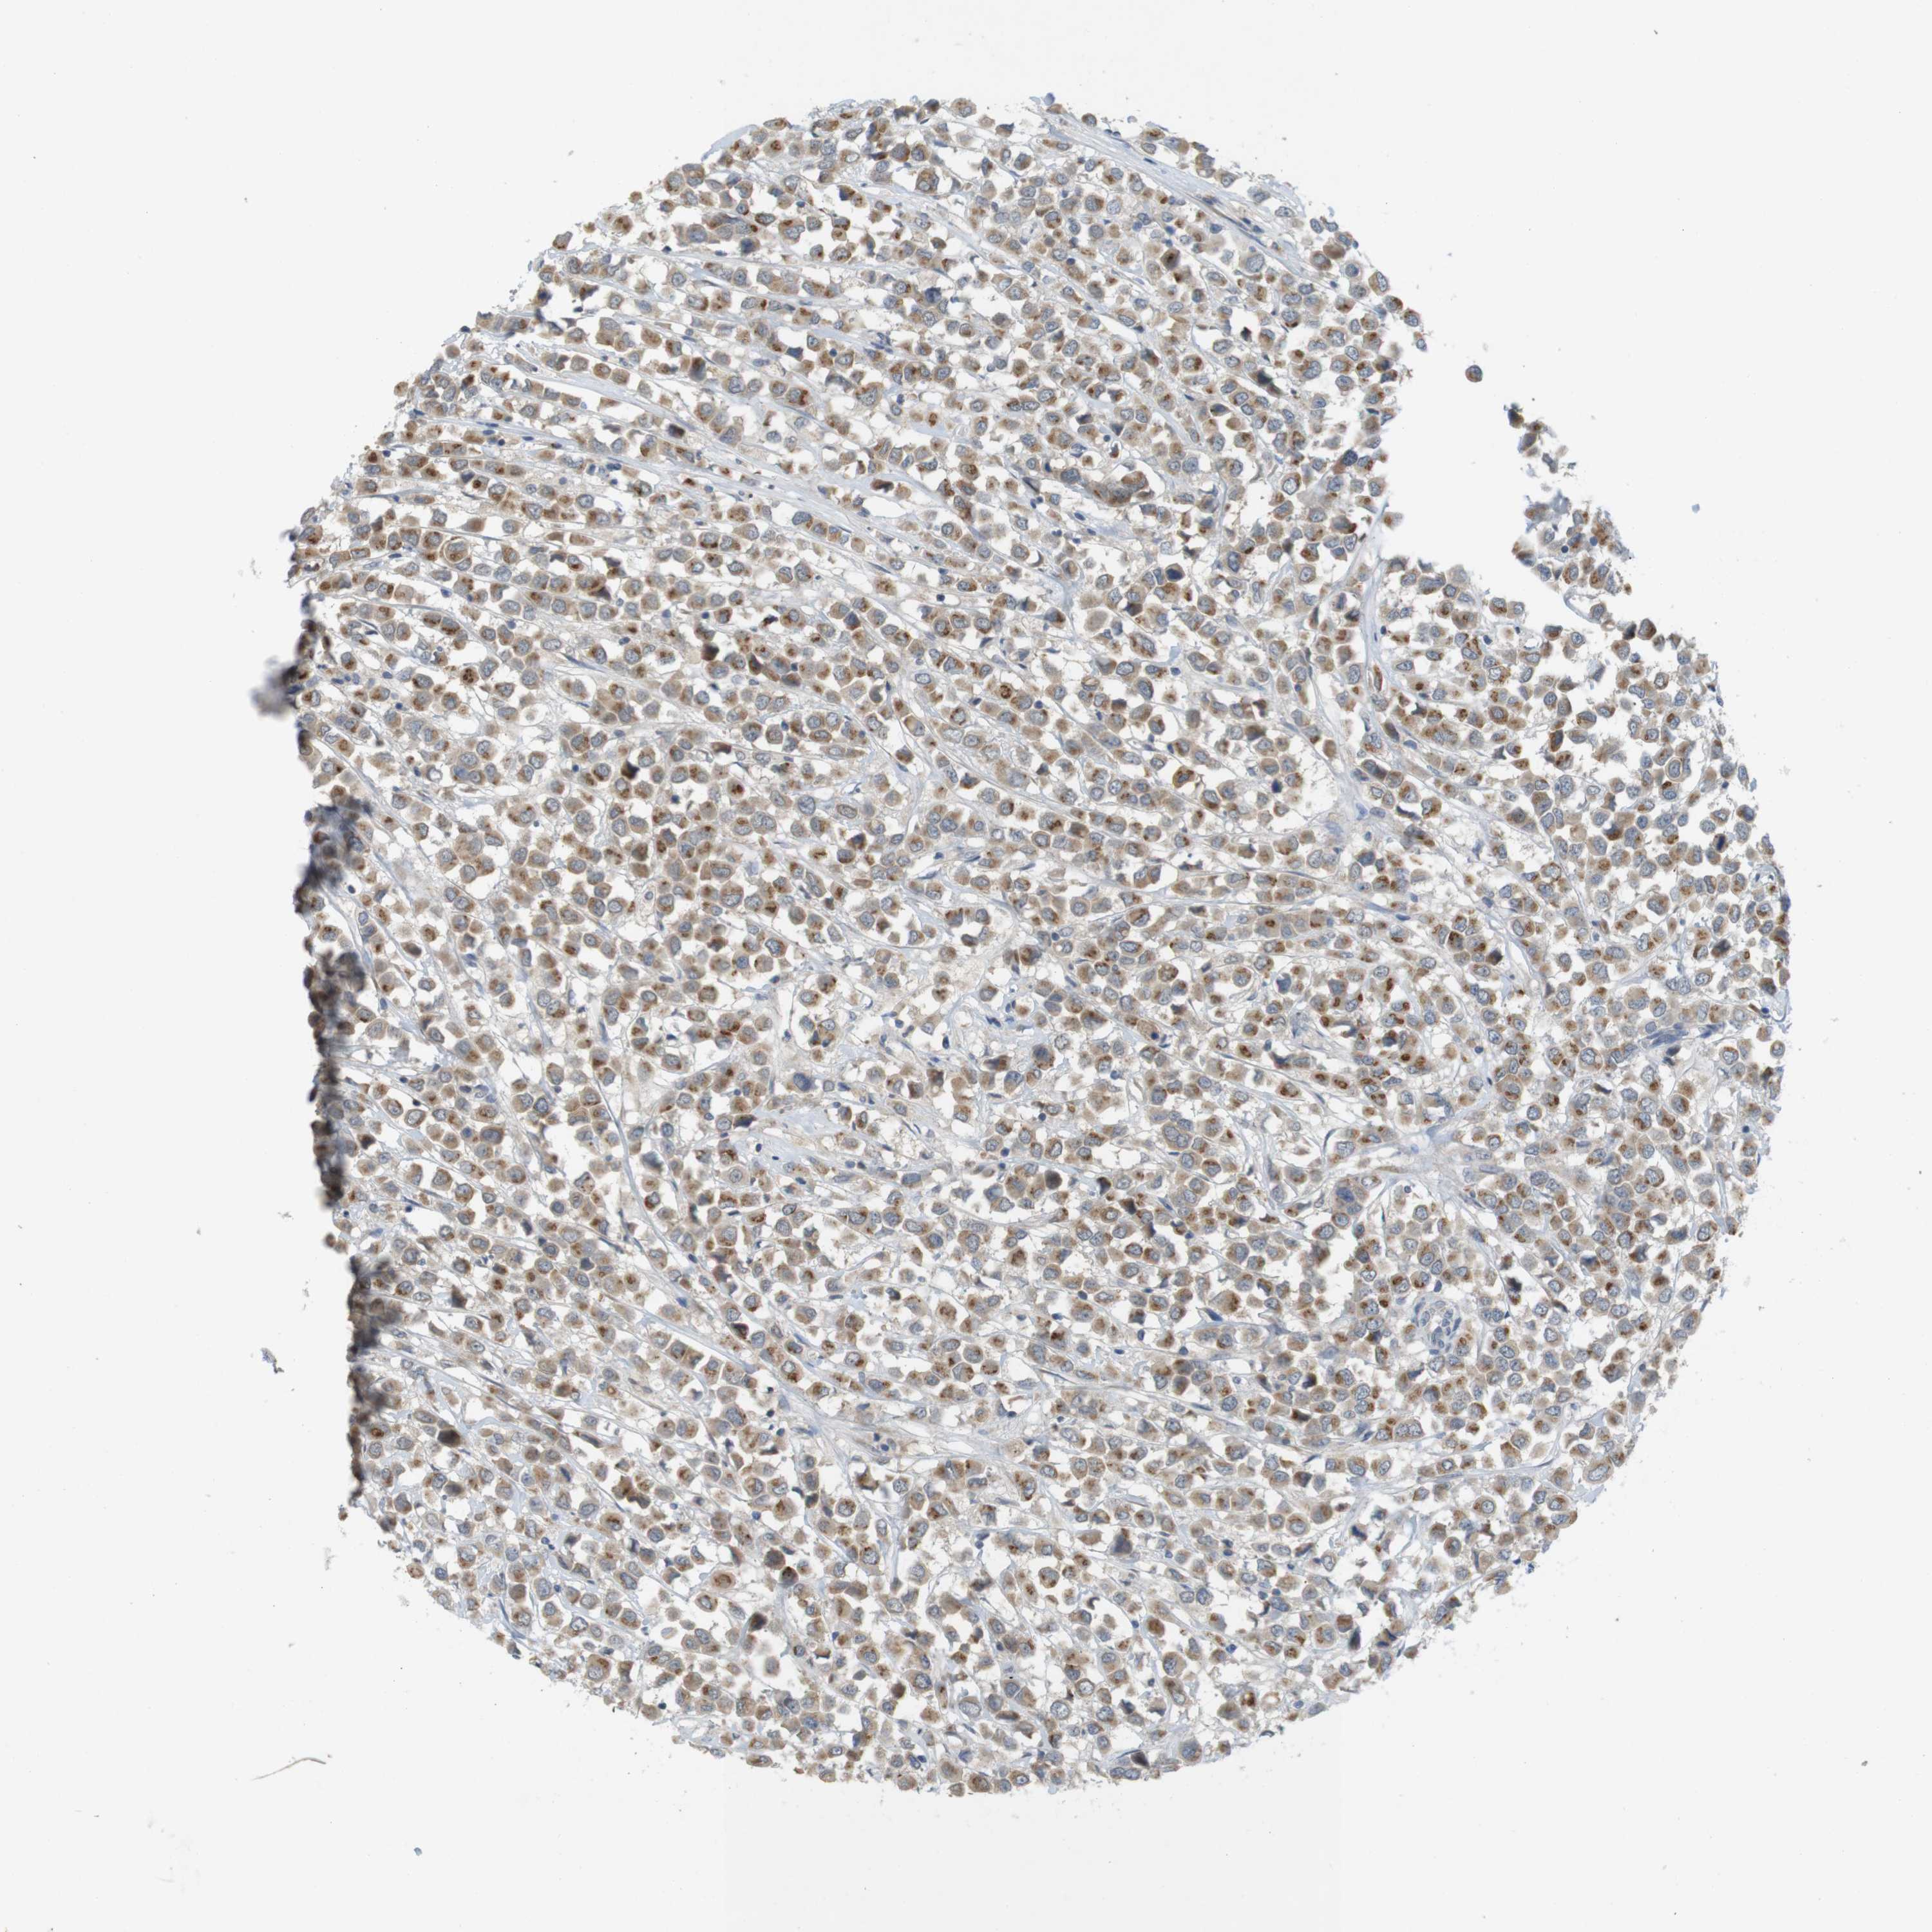

CANCER BREAST CANCER Show tissue menu

BRCA TCGA BRCA VALIDATION PROTEIN EXPRESSION

Breast cancer

Human cancer

YIPF3 is not prognostic in Breast Invasive Carcinoma (TCGA)